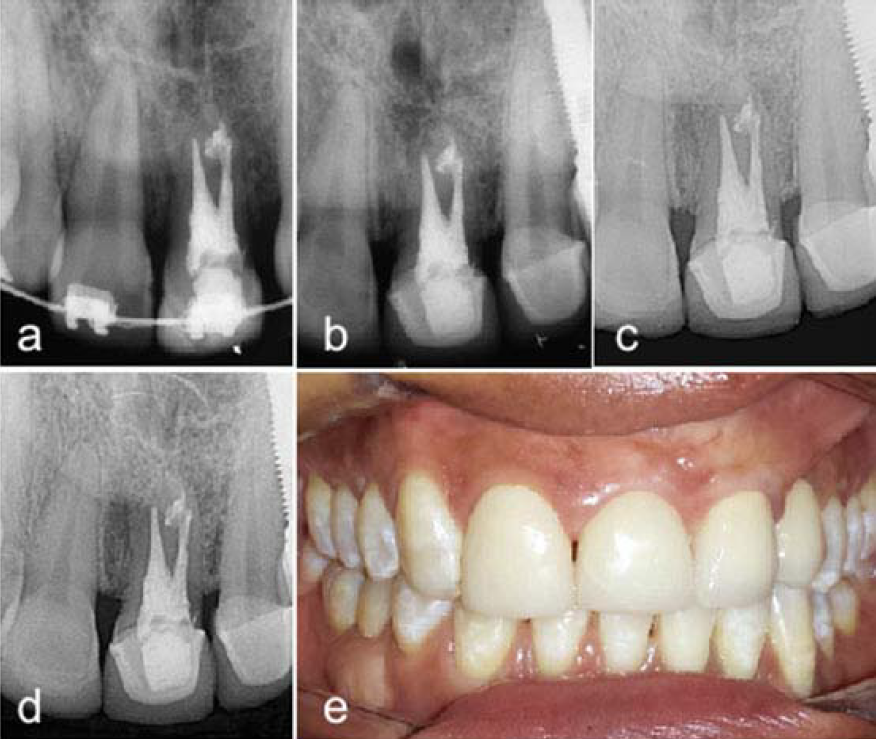

Após a proservação sequencial durante vários anos (4, 8, 13 e 17 anos) (Fig. 3, a, b, c) obeservou-se o dente funcional (Fig. 3, e), a paciente não apresentou sintomatologia e radiograficamente os tecidos periapicais apresentaram aspecto de normalidade, indicando o sucesso da terapia instituída.

a) Radiografia controle 4 anos. b) Radiografia controle 8 anos. c) Radiografia controle 13 anos. d) Radiografia controle 17 anos. e) Foto clínica de controle 17 anos.